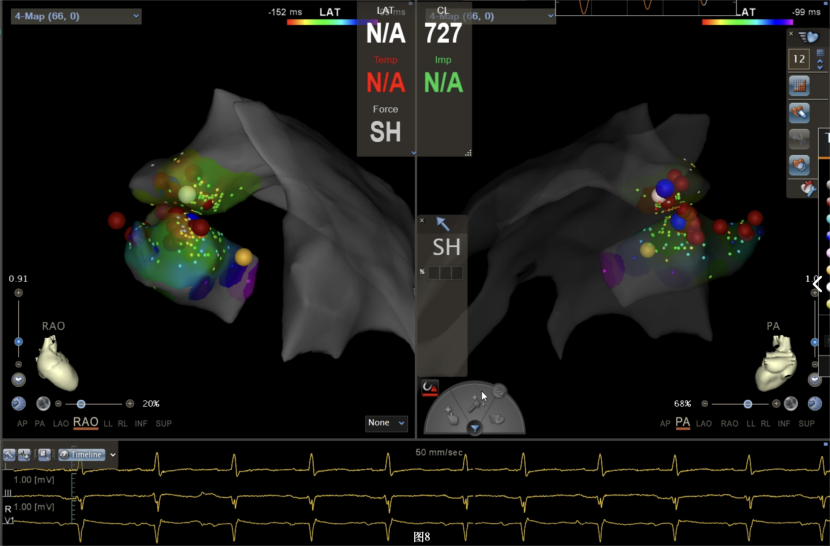

即穿刺股静脉,将消融大头送至冠状窦内,在GCV远端对应位置标测到最早点(图5绿色点)领先体表27ms,消融后早搏未能消失,周明礼评估起源点偏心外膜,能量依旧不能穿透损伤到起源点,内膜消融基本无效后,果断选择难度系数最为复杂的干性心包穿刺心外膜消融。在导丝的指引下,将消融大头送至心包层(图6),于外膜标测到靶点(图7黄色点)电位领先体表31ms,单极电位无r波且有顿挫,ssummit外膜离冠状动脉较近,比较危险,保证安全,进行了冠脉造影(图7),显示距离LAD和LCx有一定距离,相对安全,随即放电,2s室早消失,10s患者出现心率变慢,该区域走形迷走神经节,消融导致心率减慢,随后保证心率正常的情况下,消融够60s,随后观察半小时,早搏没有恢复,手术成功(图8)。经过不懈的努力,患者恢复了窦率,心脏功能也逐渐恢复正常,手术取得了圆满成功。